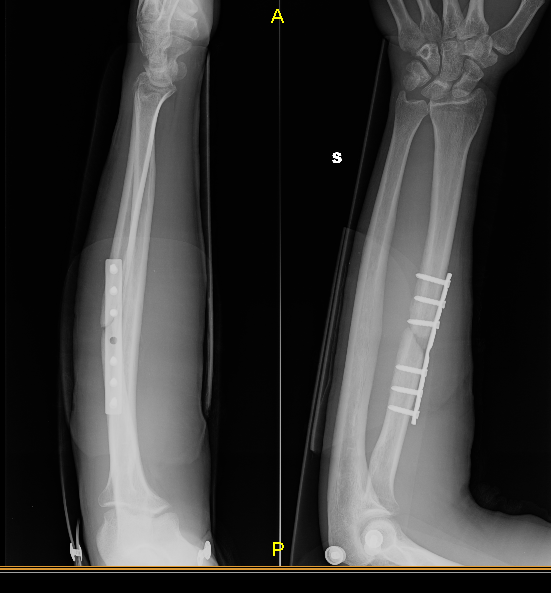

1/12/2016 - Viene effetuato intervento chirurgico , riduzione e placca a 6 viti presso una clinica , non in ospedale visto la brutta esperienza , ma in clinica e viene ingessato il braccio .

5/1/2017 - Sono passati 40 giorni dall'intervento , eseguo rx e visita , la frattura non è ancora saldata , ( allego in ordine di esecuzione l'immagine dell'rx , mi viene rimosso il gesso e prescritto un tutore precisamente " Polfit 21 " ( il tutore è lungo complessivamente 26 cm , non copre palesemente la zona fratturata ,a me è sembrato corto , non adeguato , ma il medico mi dice di stare tranquillo .

Per circa 14,16 mesi dopo l'intervento eseguo quasi ogni mese visita ed rx presso la clinica . La frattura non voleva guarire .

10/2/2018 - é passato più di un anno e la frattura non era ancora guarita , dunque eseguo visita privata in ospedale fuori regione e mi viene detto che dovevo rioperarmi , che non sarebbe mai guarita la frattura in queste condizioni . diagnosticata pseudoartrosi ( veniva refertata anche nei precedenti raggi fatti in clinica ) e suggerito intervento , innesto osseo da cresta iliaca

4/06/2018 - viene eseguito l' intervento ed ingessato il braccio . Viene rimossa la terza vite , quella che nella prima radiografia è molto vicina alla frattura ,anzi quasi dentro la frattura . Come potete notare nell rx di ottobre difatti la vite manca.

2 Considerando che la terza vite ( a partire da sopra per intenderci ) che si vede nella prima rx è stata rimossa nell'ultimo intervento , allego anche l'rx fatta dopo quest'ultimo intervento, secondo voi potrebbe essere a causa di quella vite messa malissimo , quasi nella frattura in pratica , il mancato consolidamento del primo intervento ?

una delle viti che hanno messo nel primo intervento fatto in clinica è messa praticamenet nella frattura e per quello non è guarita con il primo intervento .